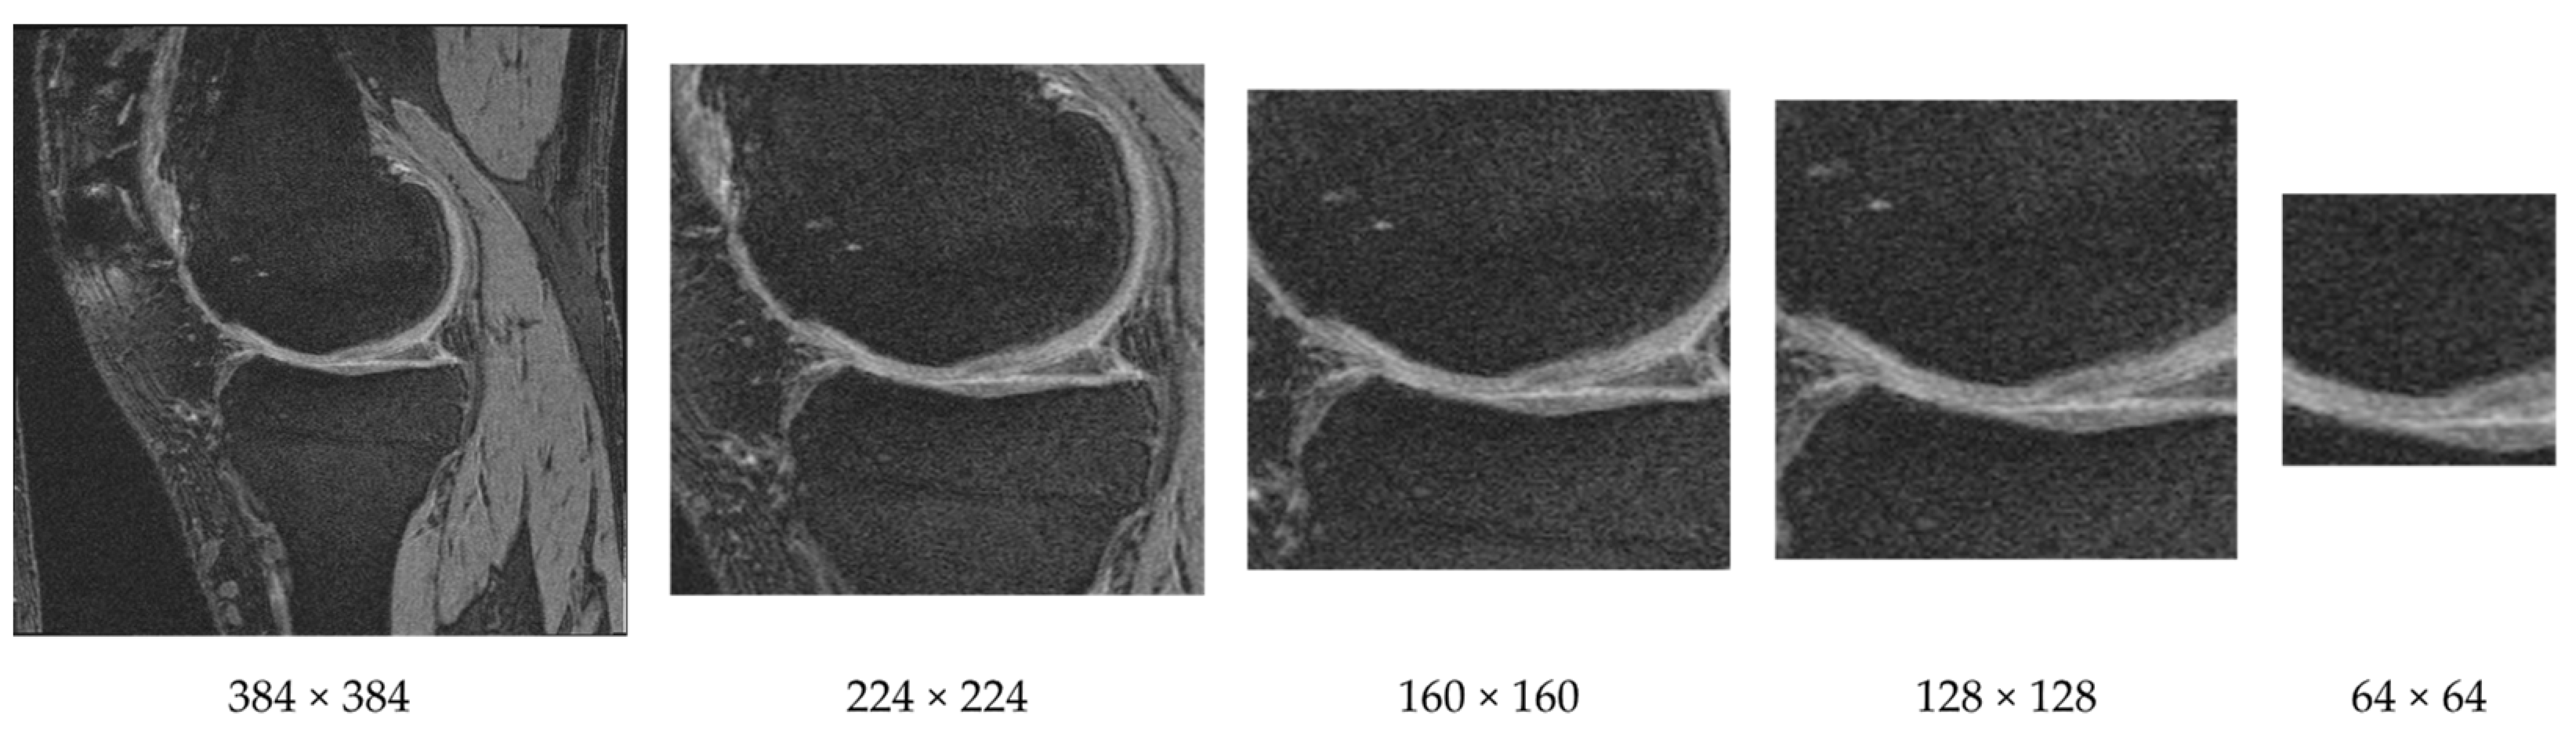

Unlike natural images where useful information could appear anywhere, in medical images, features are usually located in fixed locations. As an example, the knee MR image shown in Figure 2 contains large bone areas and many other tissues. The important indicators for knee OA are often observed near the cartilage and joint region of femur and tibia bones. Therefore, we can reduce the input dimensionality by cropping a subregion of the images.

We cropped each image as a preprocessing step that helps to keep the cartilage region while removing regions that are less informative for knee OA classification. We cropped the image (original size 384 × 384) from the center using both square and rectangular regions. An example of cropping a knee MR image to various sizes is provided in Figure 3. Through various tests we discovered that the window size of 160 × 160 achieved the highest F-measure.

Figure 2. A 2D slice from a 3D knee MR image sequence. The circled area is the cartilage region between the femur and tibia bones.